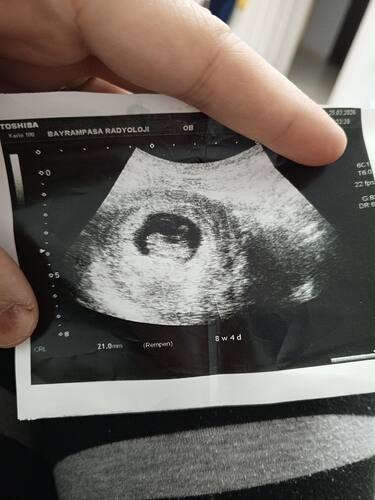

Sürekli gittiğimde erkeğe benziyor diyor doktorumuz

Ben erkek diyorum ![]()

Kız gibi sanki

Gördüm görseli, Kız gibi hissettim.